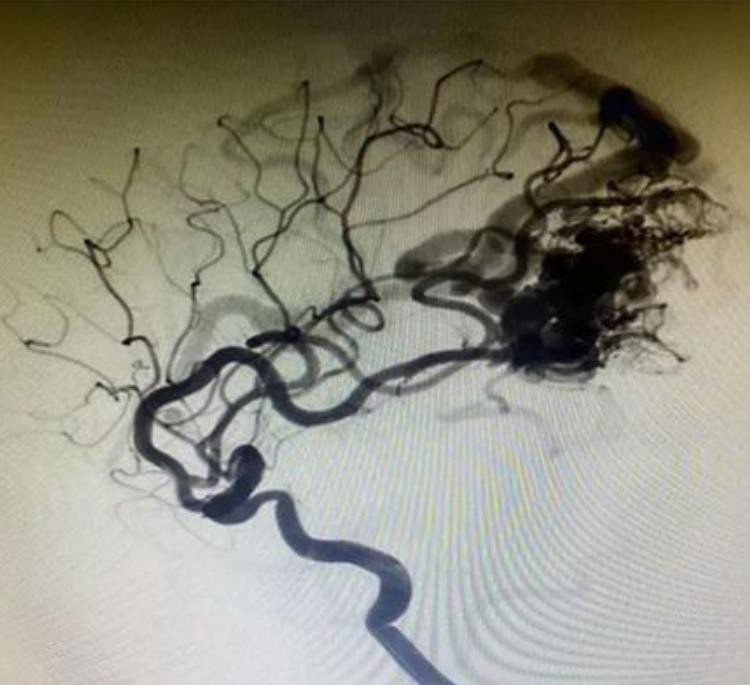

Когато лаваTmИнтракраниалната аневризми Течната емболична система контактува с кръвта или всеки воден разтвор, повърхността му незабавно ще се втвърди и ще образува защитен филм. DMSO в емболичния агент се разрежда и дифузира в кръвта, така че танталумният прах, обвит от EvOH, се утаява и се втвърдява отвън от вътрешната страна. В същото време лавата се дифузира до далеч под налягането на инжектиране. Накрая, той образува гъсто емболно тяло в положението на емболизацията.

Има по -добра дисперсия и проникване. и може дълбоко да проникне в лезията и да достигне до дисталния съд.

Танталумният прах е по -фин, по -бавно утайка и по -ясно рентгенография в сравнение с конкурентите.